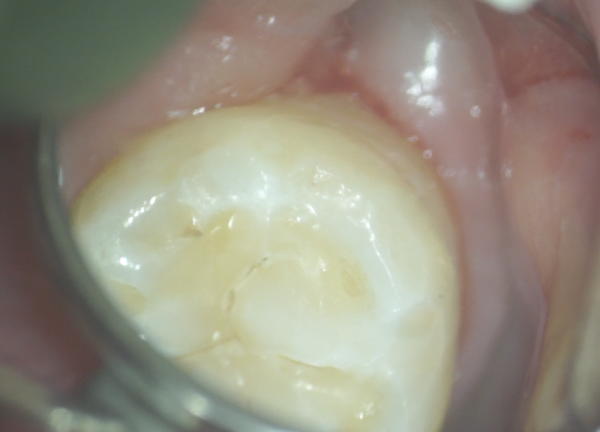

歯の奥側のみを削ったところです。

歯の奥側のみを削ったところです。

上から削れば見やすく治療もしやすいですが、少しでも削る量を少なく、噛み合わせも本来のままですので、歯の長期保存につながります。

詰め終えたところです。

詰め終えたところです。

全く段差がなく違和感がないです。

後はしっかり磨きさえすればまず虫歯になることはありません。